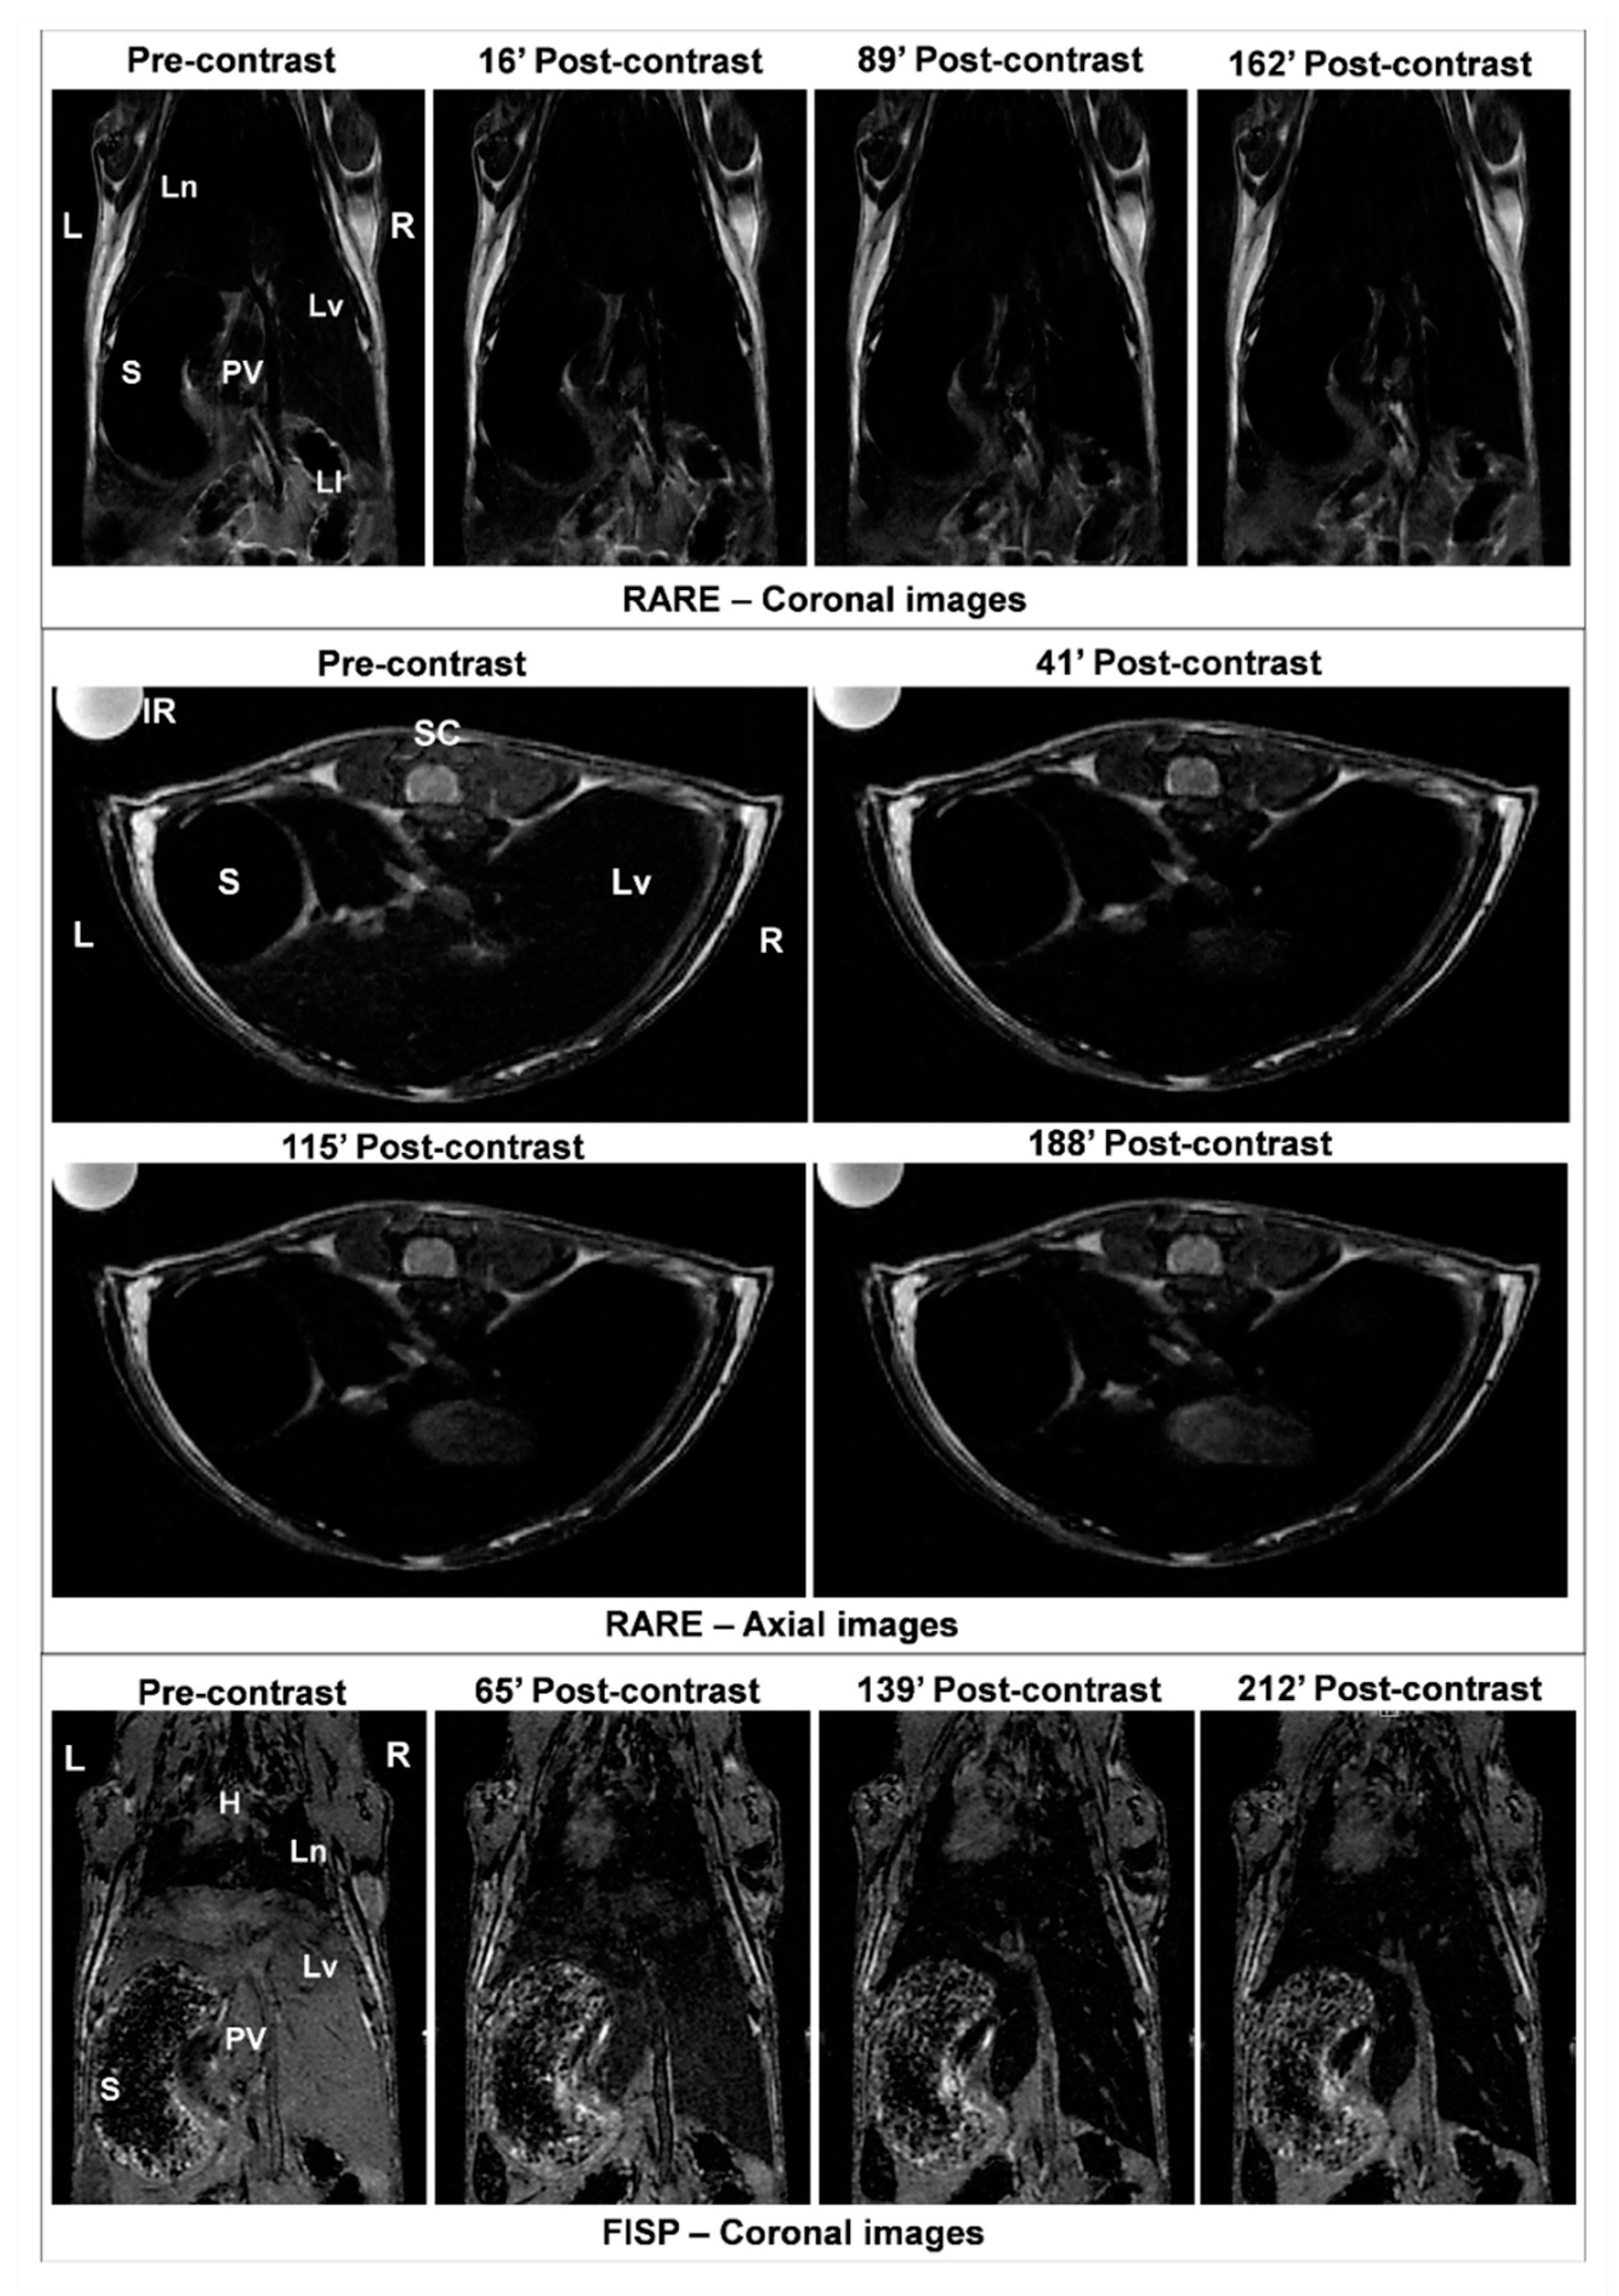

3.3. Efficacy of MNP-DSPE-PEG as Contrast Agents